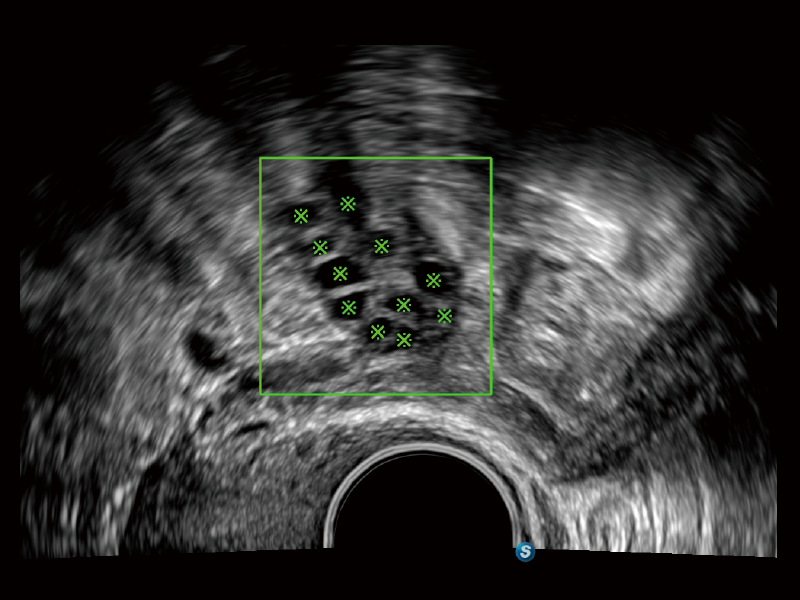

丰富的血流动力学检测技术,可在不同医疗场景中高效捕捉血流信号,助力临床诊疗。

通过创新的Matrix E自适应滤波算法,能有效滤除软组织和噪声信号,最大限度保留超低速微细血流的信号;结合超长时间域算法,极大提升细微血流的敏感性和空间分辨率,更真实的反应组织、包块的血流灌注情况。